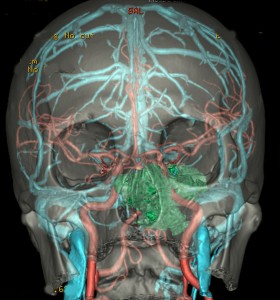

左動眼神経麻痺が急速に進行した例です。斜台から左海綿静脈洞,錐体骨尖を侵す頭蓋底軟骨肉腫です。左内頚動脈は腫瘍に取り囲まれています。

CTでは腫瘍実質部分が増強されます。不規則な骨破壊像・浸食像が特徴的です。